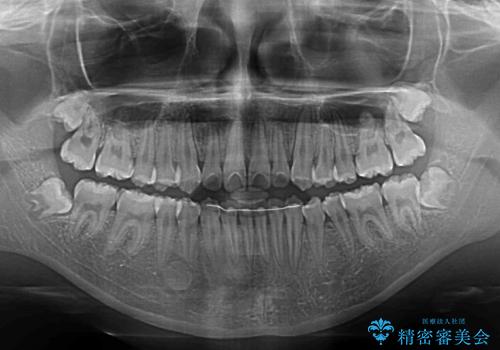

- 急速拡大装置・インビザライン

- 小児矯正の頃から診察を行っている患者様です。

上顎骨の幅が下顎骨よりも小さいので、拡大装置により骨幅を広げて上下関係を改善し、その後インビザラインにて歯並びを整えることとしました。

上下の骨幅を改善したことで、スムーズに歯列矯正を行うことができました。

インビザライン治療開始直後に遠方に引っ越しをされたため、通院間隔が長くなり、治療期間が長くなりましたが、しっかりと治療を行うことができました。